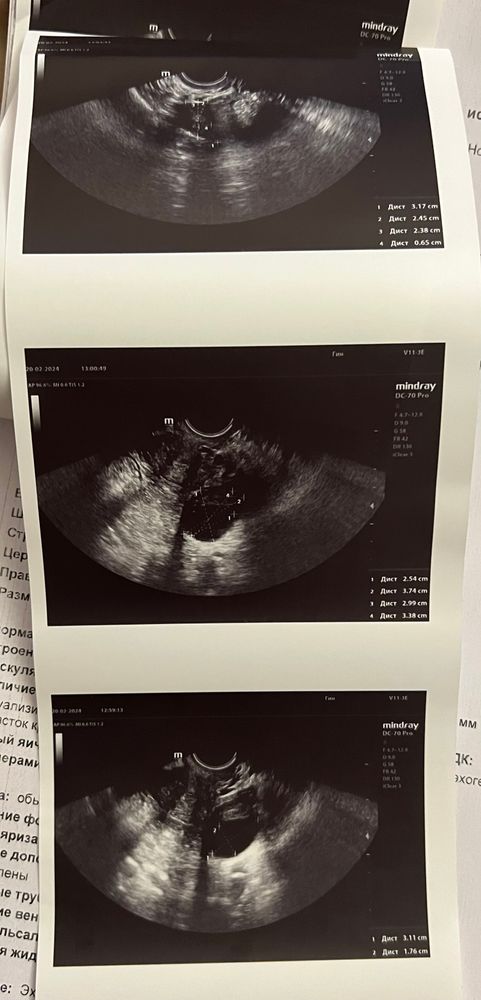

Всем привет! Девочки, помогите разобраться что означает заключение и фото , пожалуйста

гинеколог сказала овуляция была примерно 4 дня назад тк фолликул лопнувший. Свободная жидкость есть, мало.

меня смущает отсутствие ЖТ, и размеры фолликулярной кисты 3 см

Главатских Катерина, нет, в декабре был МА на фоне замершей, в январе не было овуляции. Только вот в этом цикле следить начала, на 12 дц в правом яичнике был фолликул 12 мм, а сегодня аж 31

Главатских Катерина, так вот она сказала что вероятно была 4 дня назад, поняла она это исходя из свободной жидкости и крови около фолликула, говорит фолликул перерос и вероятно лопнул. Я вот хотела узнать кто что по снимкам узи может сказать

Так ведь на снимке узи видно что фолликул лопнул, гинеколог сказала около него есть немного крови и есть свободная жидкость . Вот я не понимаю как это все